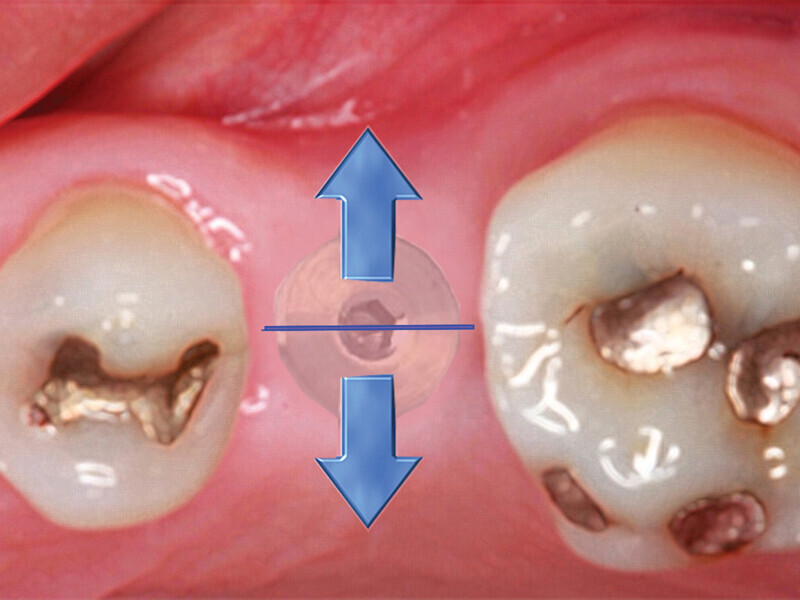

Figs. 4a: Implant to be uncovered (4a) presents with two options depending on width of attached gingiva available. Wide band of attached gingiva will remain after removal of tissue over cover screw, and the diode is utilized in a spiral pattern starting at center until fully exposed (4b). With the narrow band of attached gingiva present, an elliptical cut is made with the diode and tissue is pushed buccally and lingually to preserve the attached gingiva (4c). (Photo provided by Dr. Gregori M. Kurtzman)

Fig. 4b: Implant to be uncovered (4a) presents with two options depending on width of attached gingiva available. Wide band of attached gingiva will remain after removal of tissue over cover screw, and the diode is utilized in a spiral pattern starting at center until fully exposed (4b). With the narrow band of attached gingiva present, an elliptical cut is made with the diode and tissue is pushed buccally and lingually to preserve the attached gingiva (4c). (Photo provided by Dr. Gregori M. Kurtzman)

Fig. 4c: Implant to be uncovered (4a) presents with two options depending on width of attached gingiva available. Wide band of attached gingiva will remain after removal of tissue over cover screw, and the diode is utilized in a spiral pattern starting at center until fully exposed (4b). With the narrow band of attached gingiva present, an elliptical cut is made with the diode and tissue is pushed buccally and lingually to preserve the attached gingiva (4c). (Photo provided by Dr. Gregori M. Kurtzman)